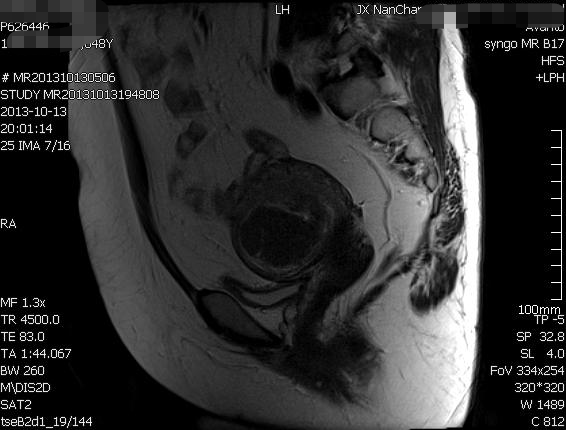

盆腔核磁宫颈前壁占位性病变,考虑肌瘤